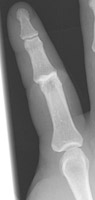

- Click on the image for a larger versionAPA radiograph of the hand. The second PIP joint is slightly overriding.